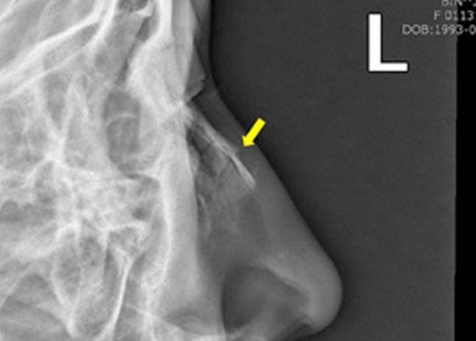

Лечебные процедуры начинаются после установления диагноза, основанного на визуальном осмотре врача-отоларинголога. Это помогает отличить перелом от симптомов сильного ушиба, которые могут быть схожи.

Специалист выполняет рентгенографию хрящей и костей лица, а также может назначить эндоскопическое исследование. На основе лабораторных анализов и диагностических данных отоларинголог, окулист и невропатолог совместно оценивают состояние ребенка и, в зависимости от степени повреждений, назначают лечение.